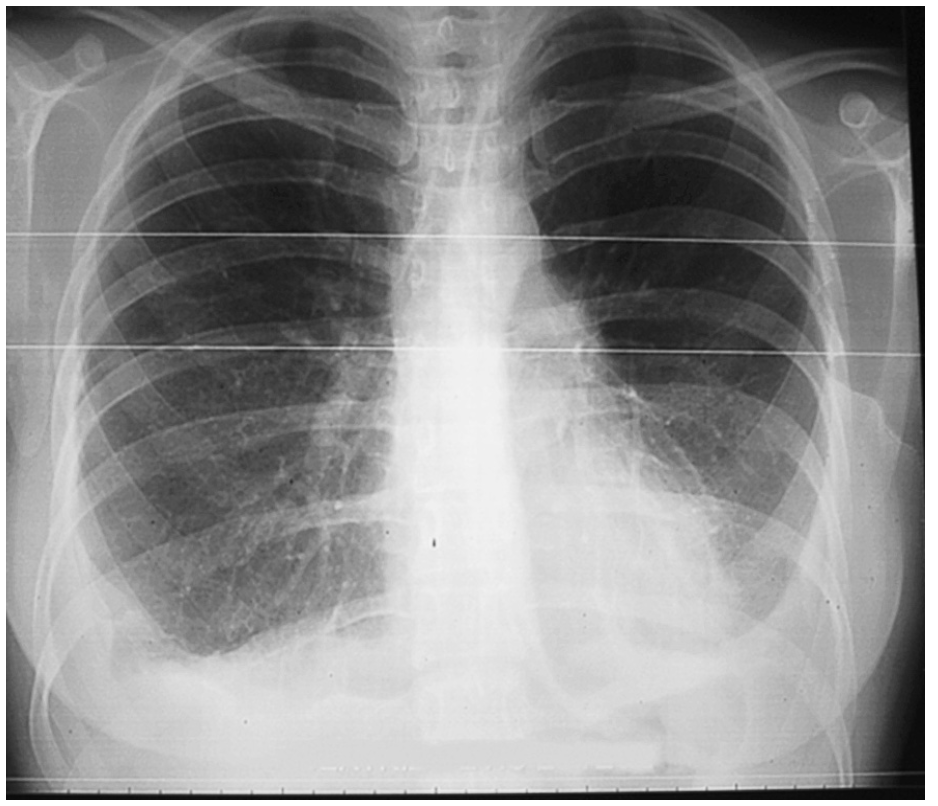

Mujer de 28 años de edad que dio a luz por vía vaginal. El parto fue traumático debido a las maniobras de presión abdominal externa inducidas por el personal sanitario. Dos semanas después del alta, la paciente acudió a urgencias por un cuadro de disnea progresiva hasta hacerse notorio a mínimos esfuerzos. En la radiografía de tórax había un derrame derecho de dos tercios y en la exploración física, semiología de derrame pleural. Se le colocó un drenaje torácico y durante varios días se obtuvo un total de 7.000 ml de líquido con aspecto quiloso y un análisis bioquímico diagnóstico de quilotórax (triglicéridos: 863 mg/dl, colesterol: 68 g/dl y presencia de quilomicrones). Al séptimo día se le retiró el drenaje, se trató a la paciente con una dieta exenta de ácidos grasos de cadena larga y 15 días tras el ingreso se le dio el alta. Tres meses más tarde, al abandonar la dieta previa, acudió de nuevo a urgencias con el mismo cuadro clínico. En la exploración física y radiológica se evidenció una recidiva del quilotórax. Fue tratada de nuevo de modo conservador hasta que, 9 meses tras el parto, la paciente fue remitida al servicio de cirugía torácica por una segunda recidiva (fig. 1). A su ingreso se le pautó una dieta absoluta y nutrición parenteral total a través de un catéter venoso central. La intervención se llevó a cabo con anestesia local y sedación: videotoracoscopia del hemitórax derecho colocando un trocar sobre el 5.o espacio intercostal en la línea media axilar, se evacuó el quilotórax (1.400 ml), se tomó una muestra para cultivo (estéril) y otra para anatomía patológica (pleuritis crónica linfocitaria) y los hallazgos en la exploración fueron: pulmón libre de adherencias, pleura parietal y mediastínica inflamatoria difusa con placas nacaradas que se biopsiaron (pleuritis crónica fibrosa). Se le realizó pleurodesis con talco en aerosol (3 g) y se comprobó la imagen en nevada tras reintroducir el toracoscopio para observar la distribución más o menos homogénea del talco antes de colocar finalmente el drenaje pleural. La evolución posterior fue favorable, con débitos de 1.800 ml en el primer día postoperatorio hasta disminuir a 75 ml al cuarto día, cuando se le retiró el tubo torácico. Seis días después de la primera intervención se realizó la segunda videotoracoscopia sobre el hemitórax izquierdo con el mismo procedimiento. Se obtuvieron 1.200 ml de derrame pleural durante la intervención. Siguió una evolución adecuada en el postoperatorio y se le retiró el tubo torácico al tercer día con un drenaje inferior a 50 ml. La paciente fue dada de alta 13 días tras la primera intervención quirúrgica y acudió para seguimiento a la consulta externa en varias ocasiones durante un año. La radiografía de control a los 10 meses de la intervención mostró un leve pinzamiento de ambos senos costrofrénicos (fig. 2) y sin cambios de posición del líquido con el decúbito. Actualmente, 3,5 años después y tras contactar telefónicamente, la paciente se encuentra asintomática, realiza su vida normal y tuvo un segundo parto hace 8 meses sin ninguna complicación ni recidiva del quilotórax.

Fig. 1. Tomografía computarizada en la que se observa el derrame pleural del quilotórax bilateral antes de la intervención.